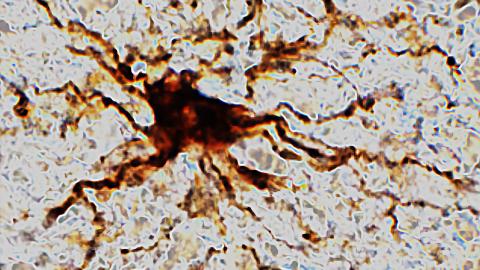

Progress of glial cells in hours after simulated deathCredit: Dachet et el./scientific reports

The third group, the “zombie” genes, were found in glial cells involved in inflammation during life. The activity of these genes was inversely proportional to the rapidly fading second group. During the test period, the zombie cells grew and sprouted long arm-like appendages for hours.

Says Loeb, “That glial cells enlarge after death isn’t too surprising given that they are inflammatory and their job is to clean things up after brain injuries like oxygen deprivation or stroke.”